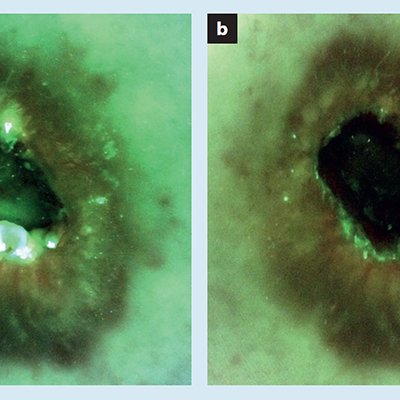

Understanding Real-Time Fluorescence Signals from Bacteria and Wound Tissues Observed with the MolecuLight i:X

Rennie, MY et al. Diagnostics 2023